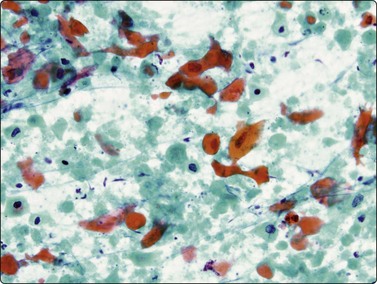

image

Fig. 8.16 Squamous cell carcinoma

Dispersed keratinizing malignant cells and necrotic debris (Pap, HP).

image image

Fig. 8.17 Squamous cell carcinoma

Irregular clumps of relatively cohesive nonkeratinizing cells; variation in chromatin density (A, MGG, HP; B, Pap, MP)

Well-differentiated squamous cell carcinoma with keratinizing cells and bizarre cell shapes is not difficult to recognise. The malignant cells are usually dispersed, especially when they are very well differentiated (Fig. 8.16); necrosis is a common accompaniment. Single keratinizing cells are the most reliable indicators of squamous differentiation; when keratinization is not obvious, a perinuclear halo within the cytoplasm and condensation of peripheral cytoplasm are helpful guides to squamous differentiation (Fig. 8.17). Non-keratinizing tumors are usually more cohesive and present as multilayered fragments. Their nuclei are usually spindle shaped or elongated with dense, irregularly distributed chromatin. There is often conspicuous variation in the degree of chromasia of nearby nuclei. Nucleoli vary in size and number, in contrast to adenocarcinoma where nucleolar morphology is more monotonous. Dense cytoplasm and well-defined cell borders are indicators of squamous differentiation, but some adenocarcinomas may have strikingly well-defined borders and very dense cytoplasm.